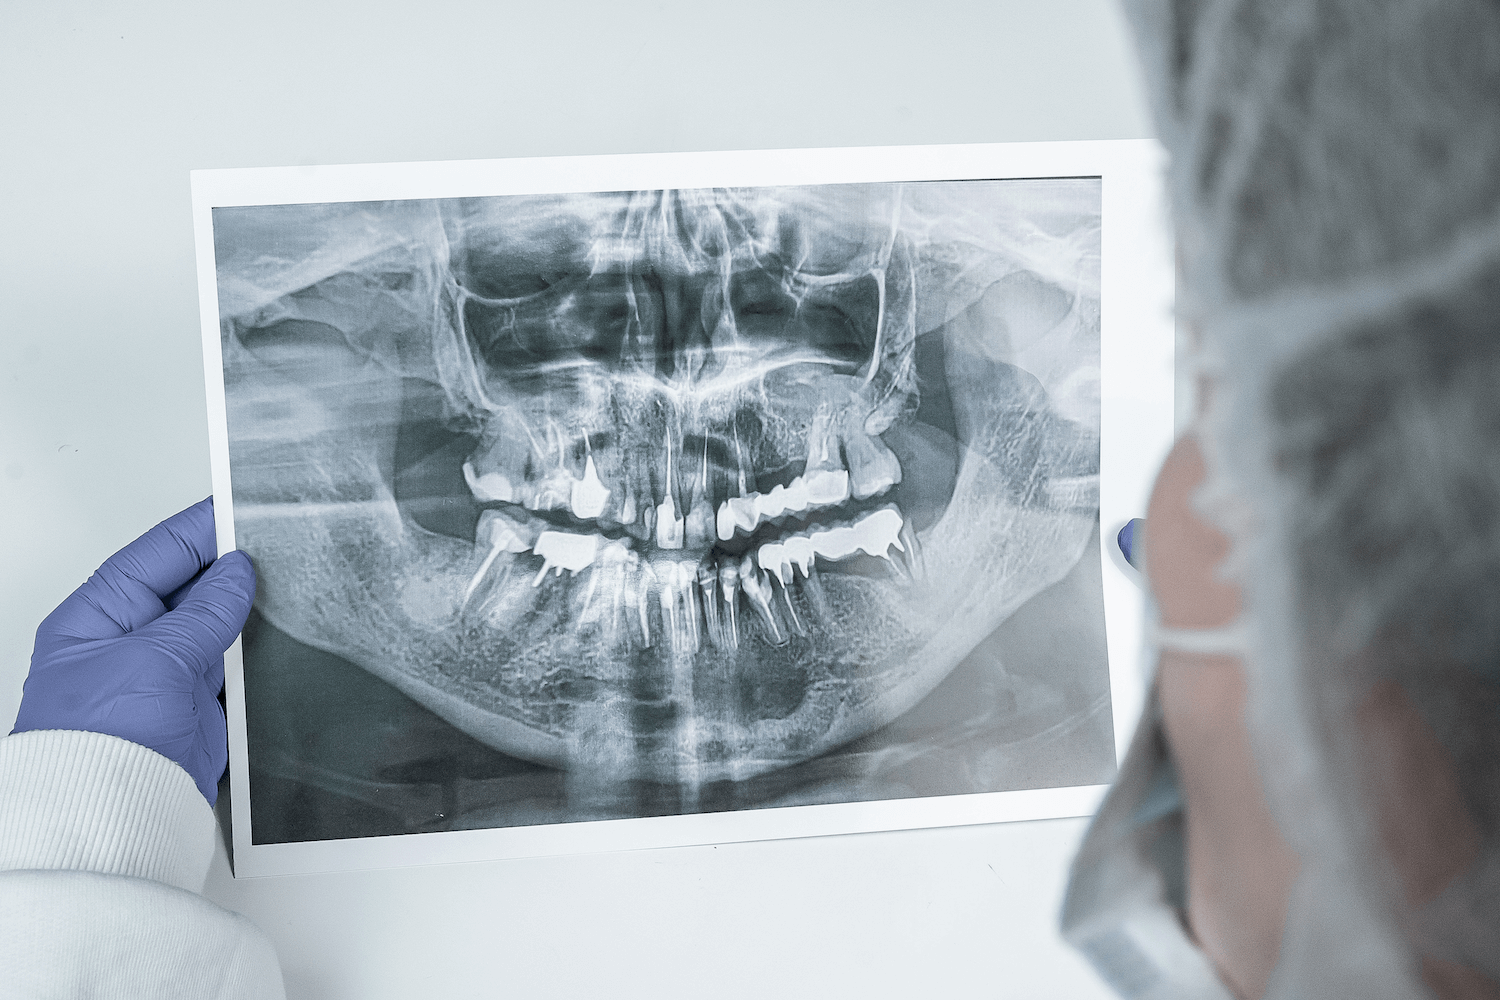

Около десяти лет назад к нашему врачу Максиму Макаренко обратилась пациентка с целью получить альтернативное мнение врача. Во время диагностики на панорамном снимке врач обнаружил интактные (здоровые) зубы на нижней челюсти и в области подбородка, в области апексов фронтальных зубов кисту с четким очертанием. Киста была достаточно большого размера, а именно от зуба 4.5 до зуба 3.5. То есть почти все зубы нижней челюсти были поражены новообразованием.

Дополнительно пациентку беспокоило онемение губы с обеих сторон, низа подбородка (из-за давления кисты на выход нерва из ментального отверстия).

После осмотра, изучения ОПТГ-снимка и выслушав жалобы пациентки, врач обнаружил зуб, вызвавший образование кисты (зуб 3.2) и предложил лечение, которое позволит сохранить все зубы. Пациентка согласилась на лечение, состоявшее из следующих этапов: